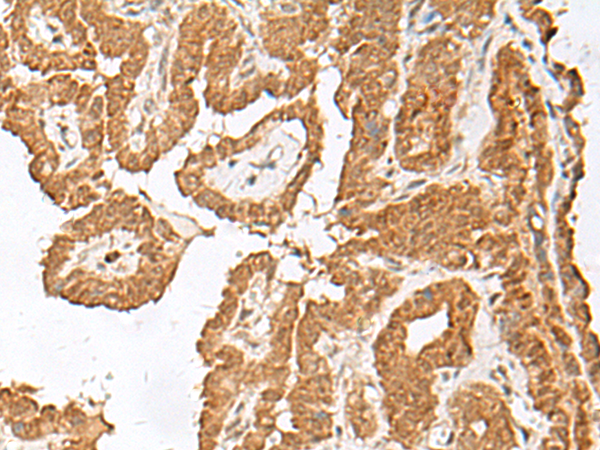

IHC positive control: |

Human esophagus cancer and Human thyroid cancer |

IHC Recommend dilution: |

40-200 |